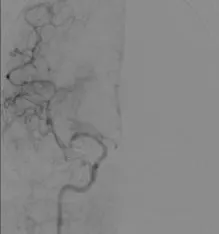

影像学表现与临床症状不匹配,发病超7小时。 DSA: 右侧颈内动脉C1段闭塞;右侧大脑中动脉M1段闭塞,颈外动脉经眼动脉向颅内代偿。

前交通动脉开放,同侧大脑前动脉通过软脑膜支代偿右侧大脑中动脉供血区域。

后循环通过软脑膜支及后交通动脉部分代偿右侧大脑中动脉供血区。